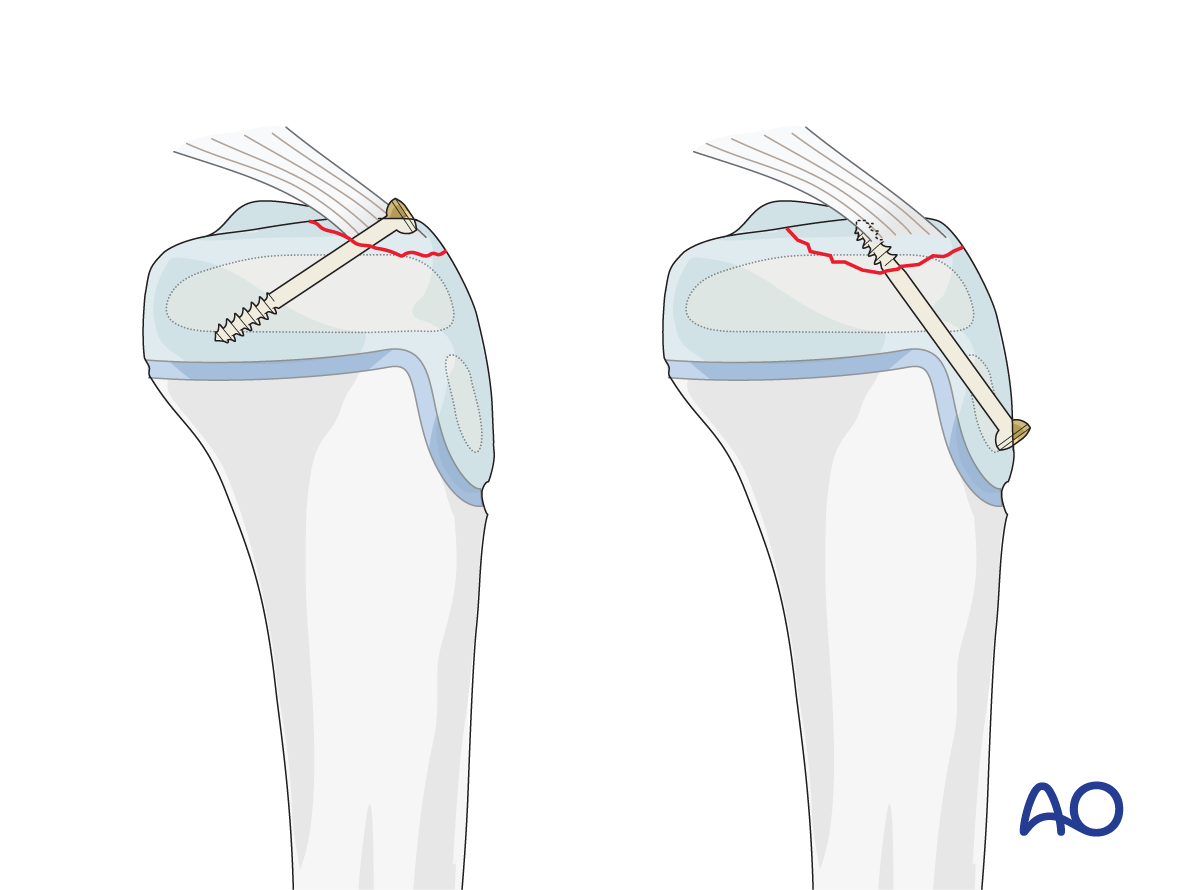

This includes detailed procedures on K-wire and screw fixation, external fixation, plate fixation, in addition to nonoperative management with casting and splinting.

Suture fixation of an avulsed tibial spine and cerclage compression wiring of an apophyseal avulsion are also covered.